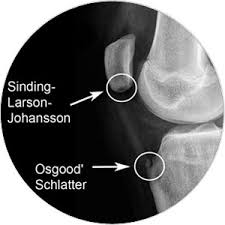

A growth plate is a layer of cartilage near the end of a bone where most of the bones growth happens. Sinding-Larsen Johansson Disease SLJ is a possible cause of knee pain in 8-to-13-year-old active individuals. Figure 1 Anatomy of Sinding-Larsen-Johansson disease.

This can occur in growth spurts or overuse from running jumping or. Sinding-Larsen-Johansson disease is a relatively uncommon condition of the knee affecting adolescents. Sinding-Larsen-Johansson syndrome is an osteochondrosis of the inferior pole of the patella and is often bilateral.

Sinding-Larsen-Johansson disease also known as Sinding-Larsen disease or Larsen-Johansson syndrome affects the proximal end of the patellar tendon as it inserts into the inferior pole of the patella. This can occur during growth spurts or overuse from running jumping or squatting. How is it treated.

Children often complain of pain and swelling at the bottom of the knee cap that may be worsened by climbing stairs running jumping deep bending of the knee or kneeling. Sinding-Larsen-Johansson Syndrome distal patella apophysitis is irritation and inflammation of the growth plate apophysis at the bottom of the patella kneecap where the patella tendon inserts.